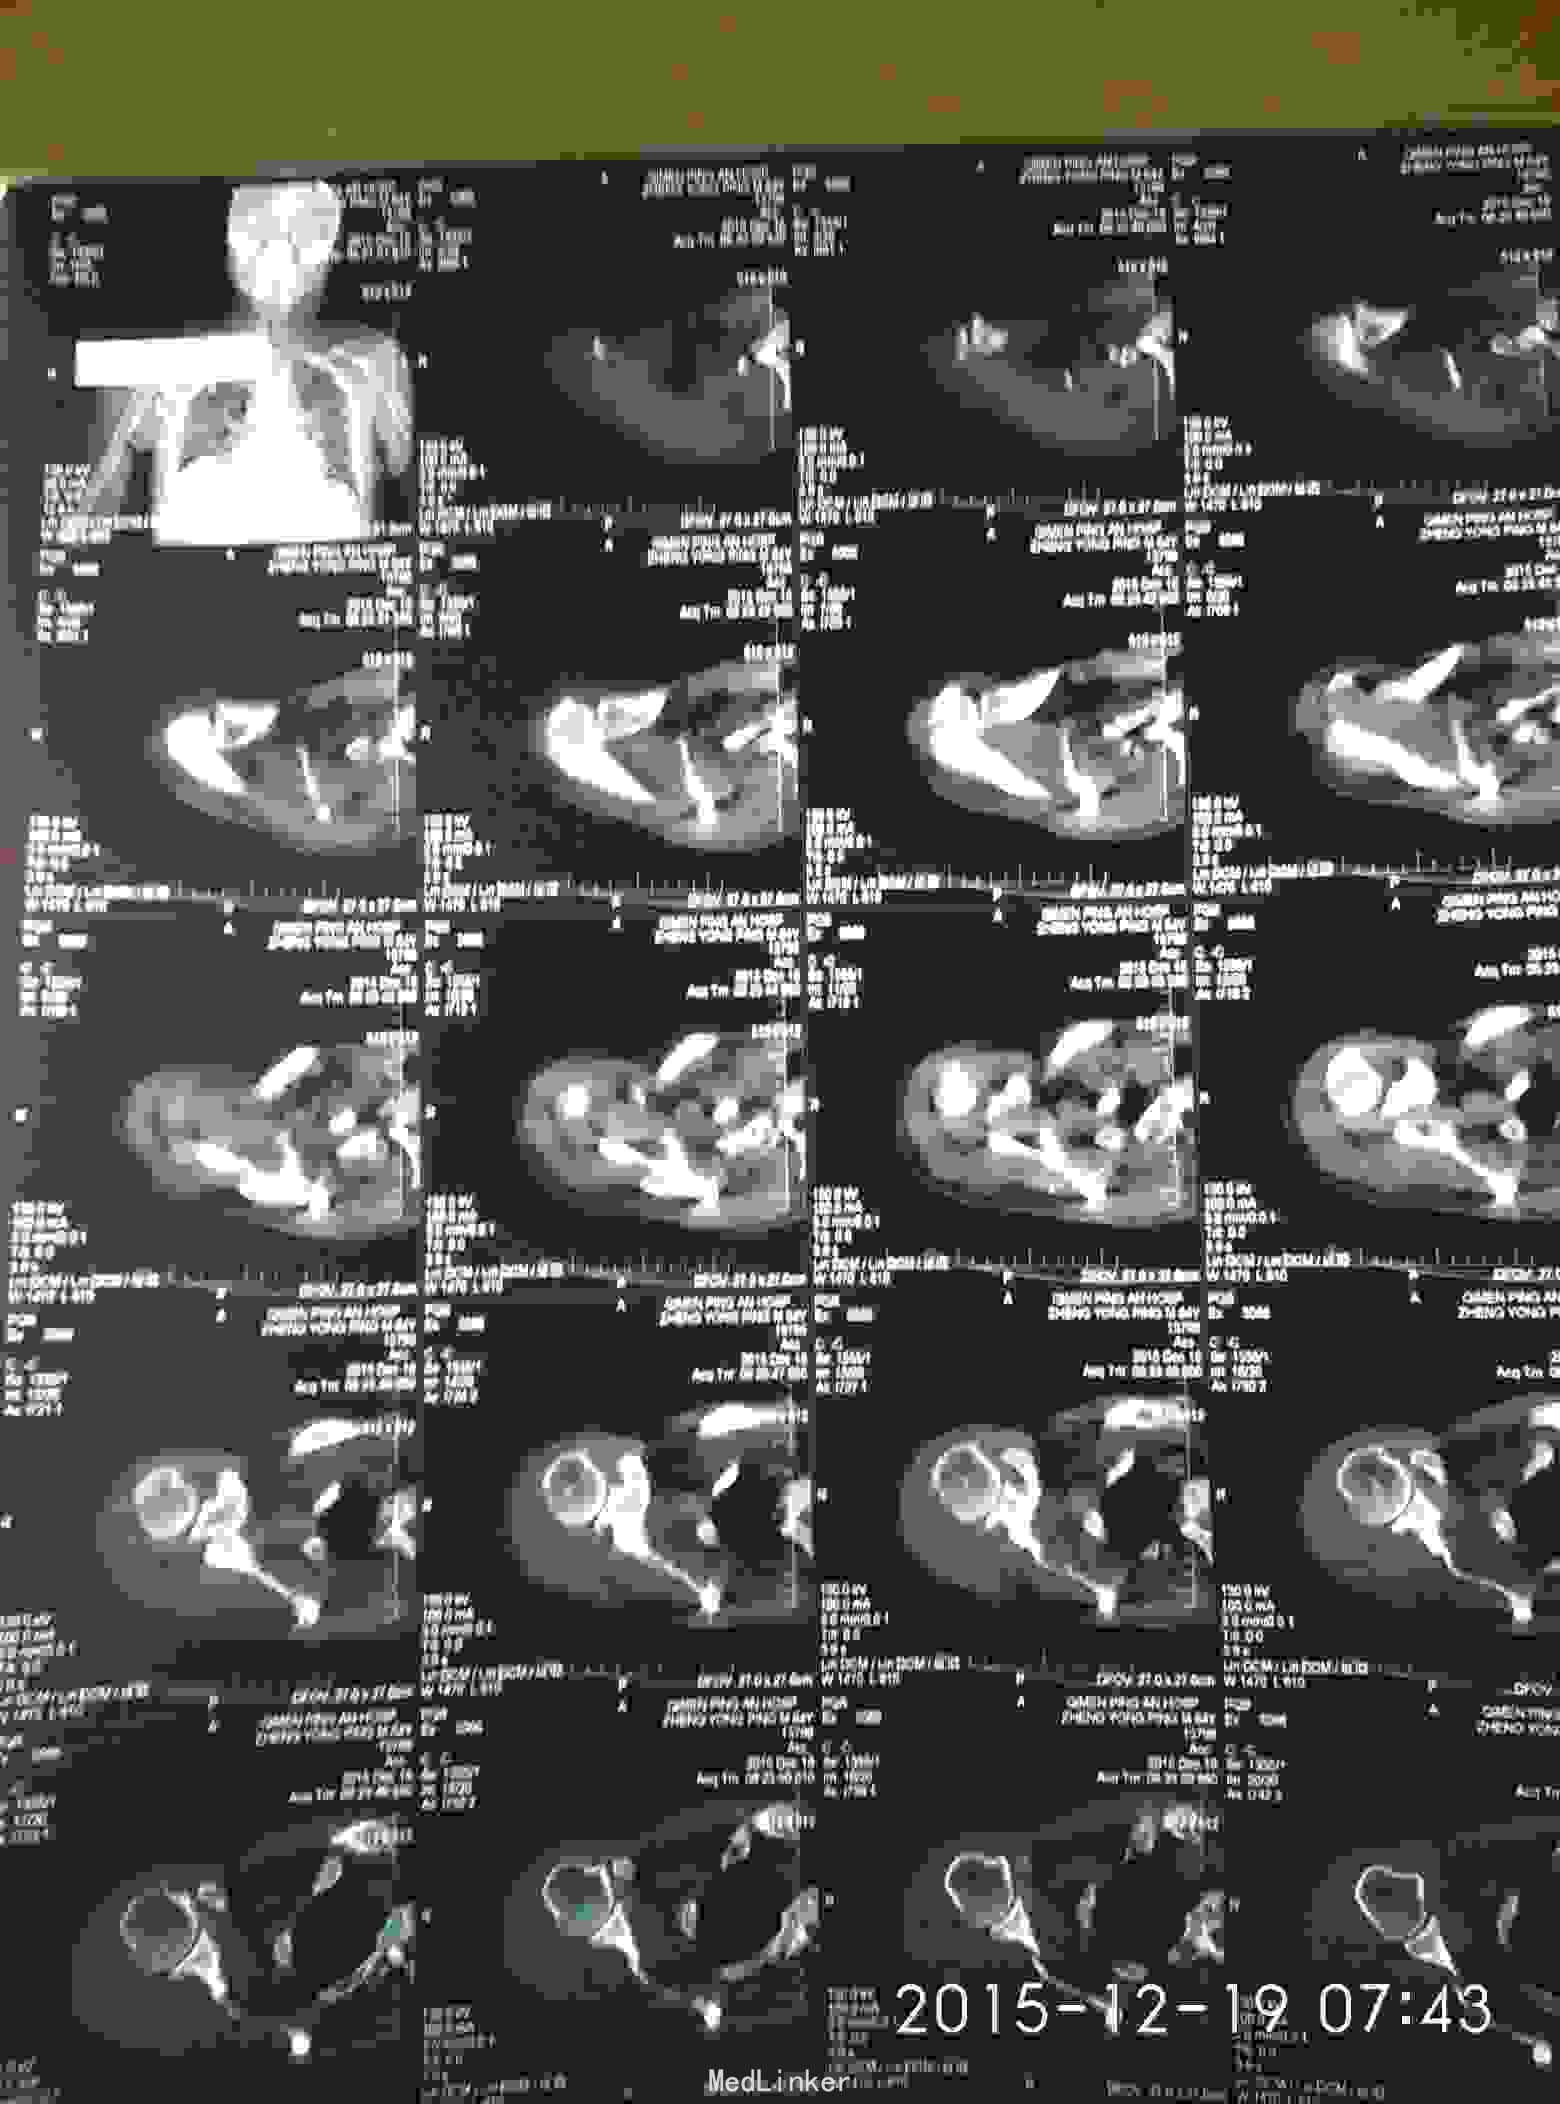

外伤致右胸疼痛及右肩疼痛,活动受限1天入院。去年右肩胛骨骨折在外院行切开复位内固定术。

胸廓挤压试验阳性,右肩峰压痛阳性,右肩主动活动受限,外展约30度。x片及CT示右肩峰骨折及肩胛骨骨折,右第6.7.8.9肋骨骨折。

右肩峰骨折,右肩胛骨骨折,右第6.7.8.9肋骨骨折